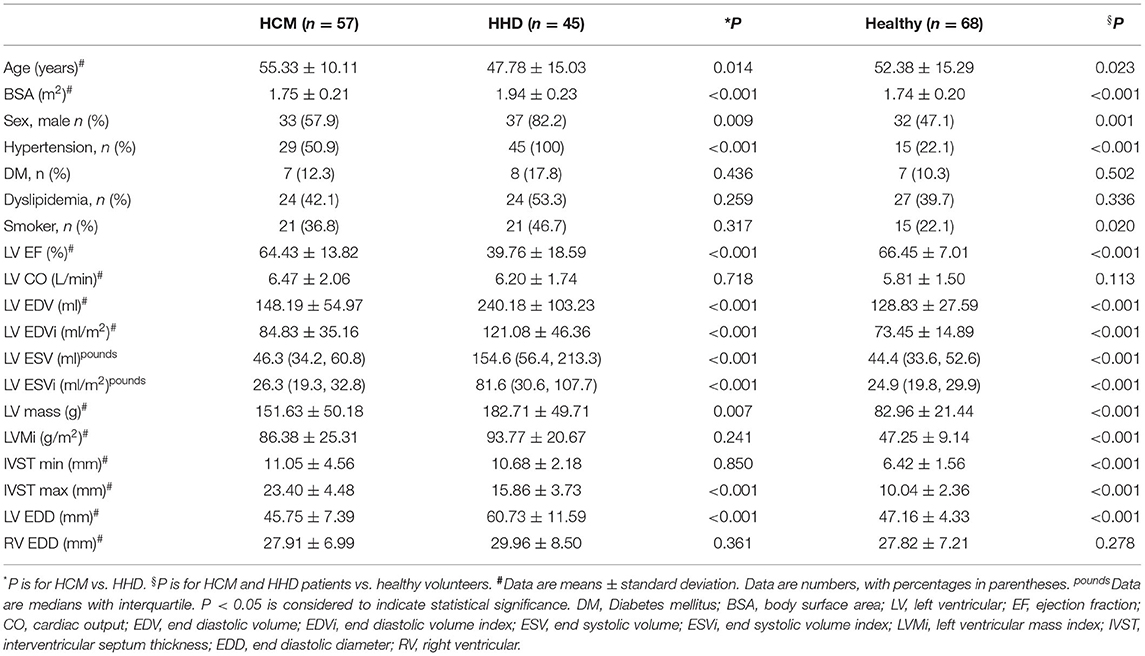

The study cohort consisted of 170 participants, including 57 patients with HCM (33.5%), 45 patients with HHD (26.5%), and 68 healthy volunteers (40%). Clinical characteristics and basic CMR parameters of the HCM, HHD, and healthy group are given in Table 1. In comparison to patients with HHD, patients with HCM were older (P = 0.014), less male (P = 0.009), had smaller body surface area (P < 0.001), and lower incidence of hypertension (P < 0.001). There was no statistical difference between the HCM and HHD group in terms of prevalence of diabetes mellitus, dyslipidemia, and smoker (all P > 0.05).

Cardiac Function by Cardiovascular Magnetic Resonance

Compared with patients with HHD, patients with HCM had a higher ejection fraction (64.43 ± 13.82 vs. 39.76 ± 18.59%, P < 0.001). Those with HCM also had a lower LV end-diastolic volume index (EDVi) (84.83 ± 35.16 vs. 121.08 ± 46.36 ml/m2, P < 0.001) and lower LV end-systolic volume index (ESVi) [26.3 (19.3, 32.8) vs. 81.6 (30.6, 107.7) ml/m2, P < 0.001]. As for maximum interventricular septum thickness (IVST max), there were higher values in patients with HCM when compared with patients with HHD (23.40 ± 4.48 vs. 15.86 ± 3.73 mm, P < 0.001). The LV end-diastolic diameter (EDD) of patients with HCM was 45.75 ± 7.39 mm, which was lower than that in patients with HHD (60.73 ± 11.59 mm, P < 0.001). There were no significant differences regarding CO, LVMi, and right ventricular EDD between the two groups of LVH.